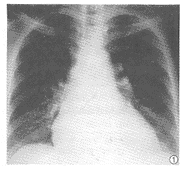

肺内网状结节影:(1)肝硬化组位于肺基底部,呈斑点状或结节状影,散布于增粗的网格状肺纹理之中,互不融合,范围局限(图1)。(2)对照组肺纹理走行及分支正常。

图1 肝硬化失代偿期,胸片示右下肺网状结节影

位于肺基底部中等大小的斑点状或网状结节阴影是肝硬化患者肺部异常改变的典型表现,在本研究中,55%的肝硬化组患者有此表现,而对照组仅为9.5%。有作者将肝硬化失代偿期患者肺内网状结节阴影视为肺间质炎症[3]。就本组资料分析,多数患者的临床、实验室检查和X线表现特点均不支持此诊断。笔者认为造成肺内网状结节阴影的因素可能为:(1)肺血流量增加,毛细血管通透性增高导致肺基底部局限性水肿。(2)肺血管局限性或弥散性扩张。上述改变非肝硬化患者所特有,亦可发生于肺纤维化或肉芽肿等间质性疾病[1],可通过肺功能测定、血管造影或CT检查将其区分。